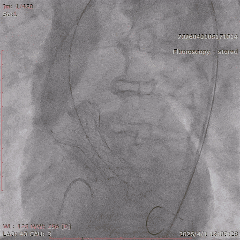

冠脉治疗后一周,张老先生整体状态平稳,进入主动脉瓣置换阶段。团队从股动脉建立通道,将人工瓣膜送至主动脉瓣位置。结合术前评估结果和术中情况,这次手术未进行球囊预扩张,而是直接完成瓣膜释放。

术中,因患者主动脉弓形态较复杂,器械通过一度受阻。团队根据术中情况及时调整策略,最终顺利完成过弓、跨瓣和瓣膜释放。造影及经胸超声显示,瓣膜位置理想、功能良好,左右冠脉血流通畅,未见瓣周漏及血管并发症。

▲根部造影

▲最终瓣膜造影

▲入路检查